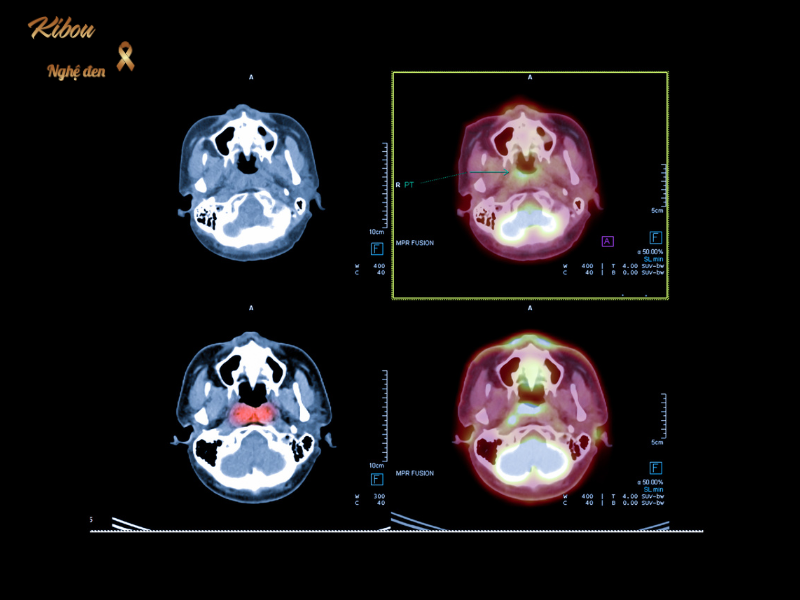

ĐAU HỌNG, Ù TAI KÉO DÀI MÙA LẠNH: CẢNH GIÁC UNG THƯ VÒM HỌNG

Nhiều người coi việc nghẹt mũi, ù tai mùa lạnh là do viêm xoang hay trúng gió. Nhưng nếu triệu chứng kéo dài trên 2 tuần, hãy cẩn trọng với Ung thư vòm họng – căn bệnh đứng đầu trong các loại ung thư vùng đầu cổ tại Việt Nam.

Nội soi với dải tần ánh sáng hẹp (NBI) giúp bác sĩ nhìn thấy sự tăng sinh mạch máu bất thường của khối u ngay từ khi nó chưa lồi lên bề mặt, giúp phát hiện bệnh ở giai đoạn rất sớm.